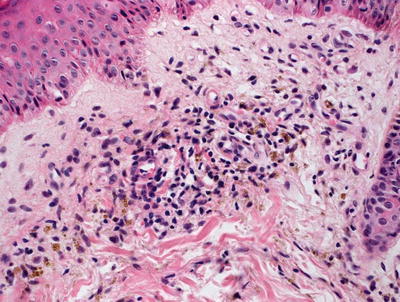

Fig. 5.6

Perivascular macrophages filled with golden brown refractile pigment granules are seen in pigmented purpuric eruptions